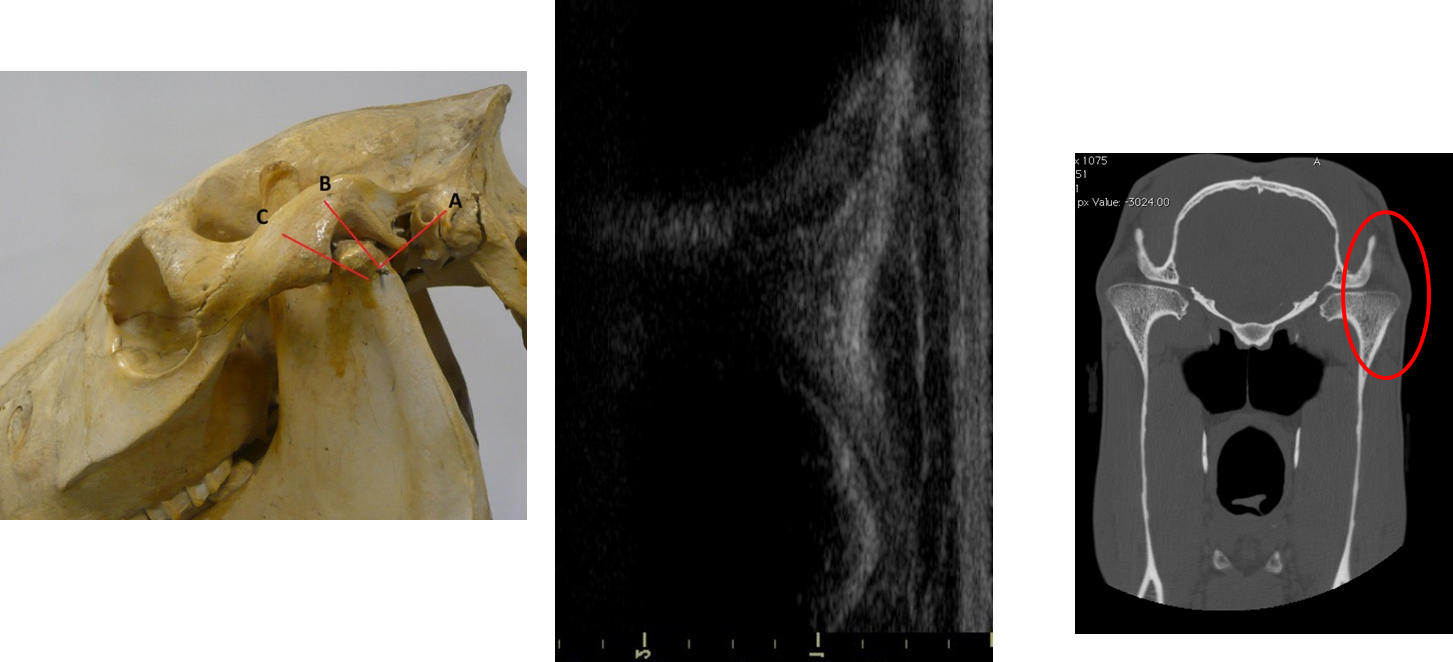

What are the features of ultrasonography as an imaging technique of the head?

Widely available

Bony skull limits its use in assessment of some areas of head

When is ultrasonography used in the head?

Ophthalmic

Soft tissue swellings external to the skull

Assessment of skull bones / temporomandib joint

Larynx

What are the major advantages of CT?

Gold standard diagnostic test

Affordable & cost effective

Cross sectional images

Superior resolution

Tissue density measurement

What is CT indicated for?

Dental disease

Masses within the paranasal sinuses / nasal passages

Trauma